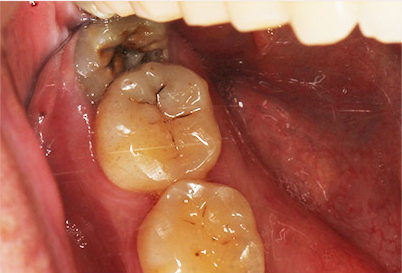

잇몸 속에 누워 있는 사랑니의 경우 인접치아에 충치나 외흡수를 발생할 수 있습니다.

이렇게 치아뿌리쪽에 생긴 충치나 외흡수는 인접치아를 뽑게 만들 수도 있습니다.